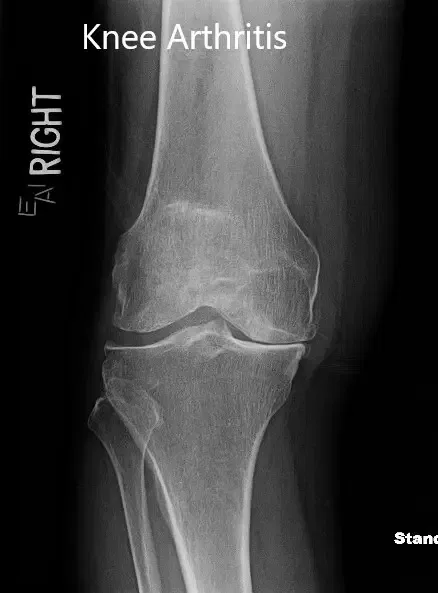

Los resultados de imagen revelaron una osteoartritis tricompartmental severa de la rodilla. Dado que su estilo de vida limita el dolor de rodilla, le recomendaron un reemplazo total de rodilla con instrumentos personalizados. Los riesgos, beneficios y alternativas se discutieron extensamente con el paciente. Él estuvo de acuerdo con el plan.

Radiografía preoperatoria que muestra la vista anteroposterior y lateral de la rodilla derecha.

Radiografía preoperatoria mostrando la vista comercial de ambas rodillas.